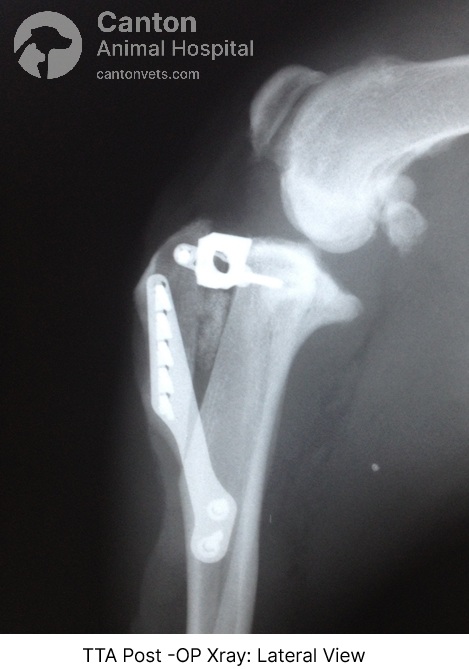

Tibial Tuberosity Advancement (TTA) Surgical Technique

Tibial Tuberosity Advancement (TTA) is a specialized orthopedic procedure designed to stabilize the knee joint in dogs suffering from a cranial cruciate ligament (CCL) tear. Unlike traditional ligament repair methods, TTA modifies the knee’s biomechanics, eliminating cranial tibial thrust to restore joint stability.

A sagittal saw is used to perform an osteotomy (controlled cut) of the non-weight-bearing portion of the tibia.

Pre-drilled attachment points are created for the TTA tension plate.

A custom-sized titanium cage is placed at the proximal end of the osteotomy site.

The tibial crest is secured with a tension plate, and a bone graft is inserted to promote healing.

Cranial tibial thrust is eliminated, ensuring the knee is stable.

Follow-up X-rays at 8 weeks—Assess bone healing before increasing activity levels.